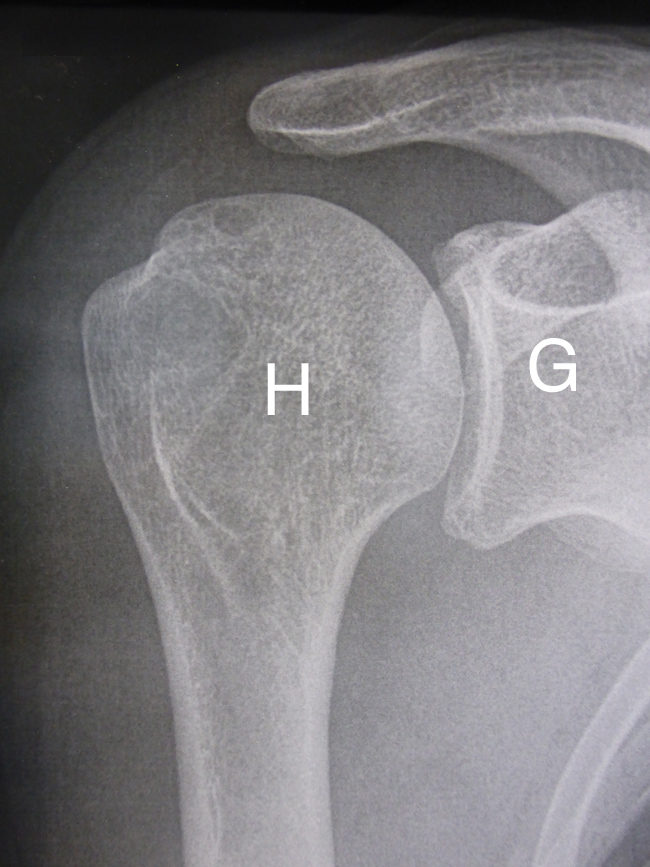

Sur cette radiographie de face d’une épaule droite l’humérus (H) est fracturé et n’est plus en face de la glène de l’omoplate (G).